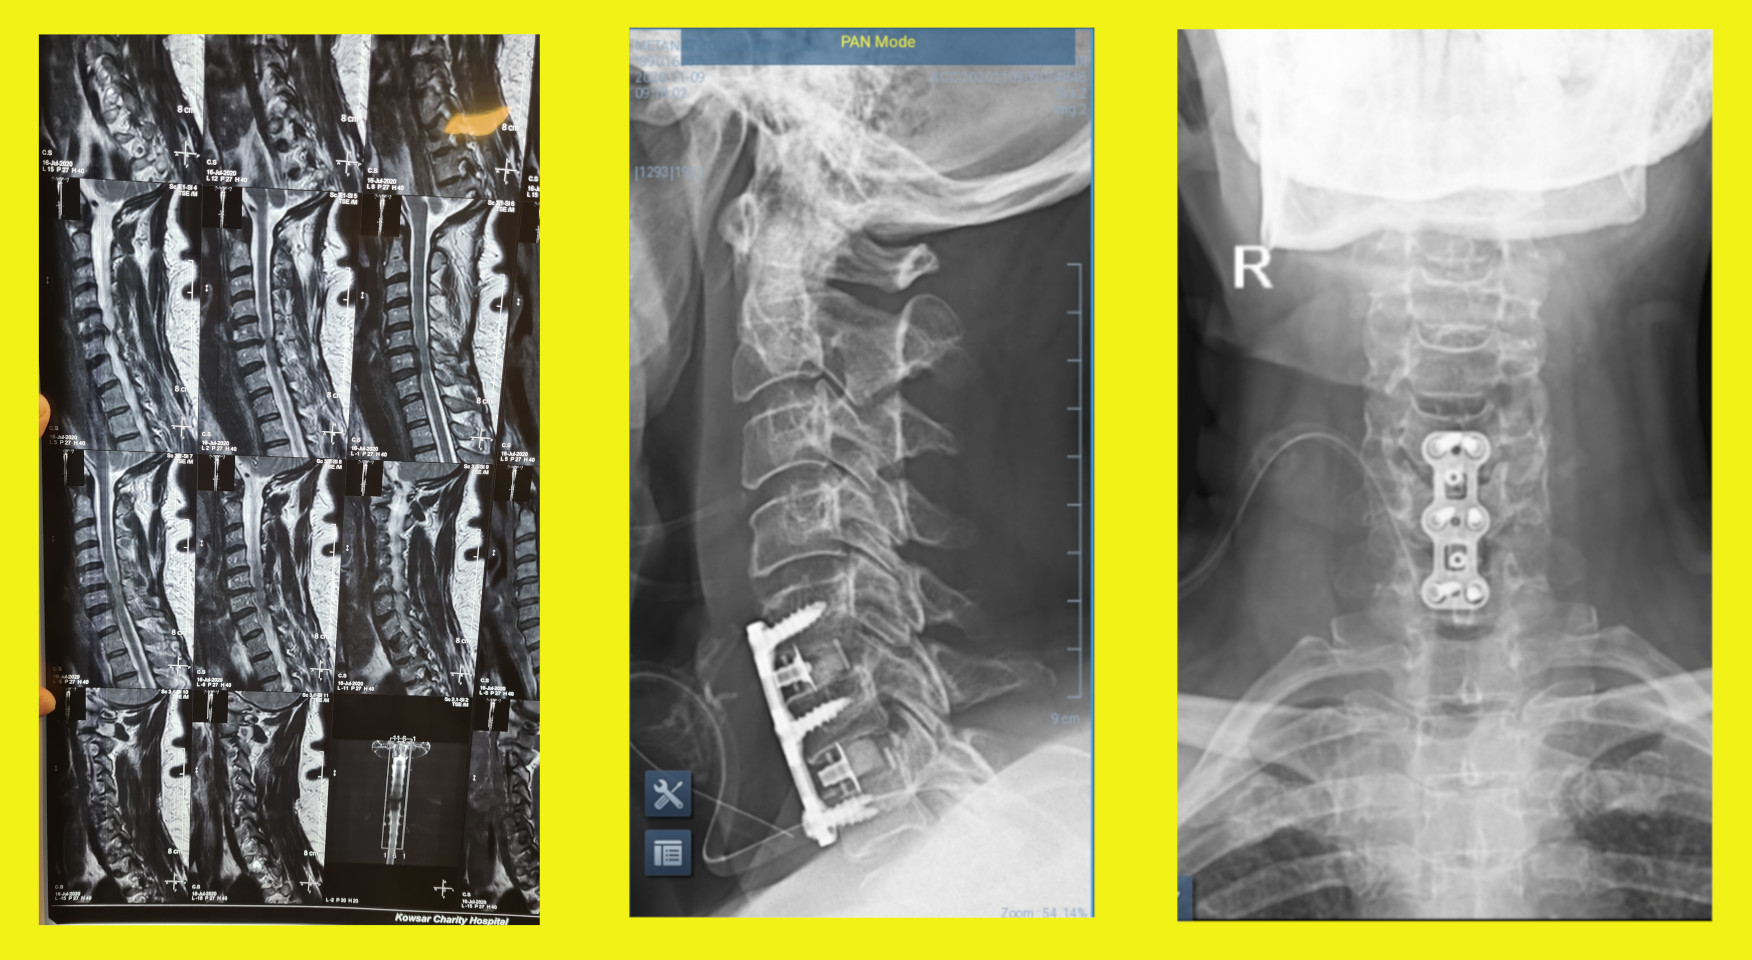

عکس بالا سمت چپ بیماری را نشان میدهد که دیسک پاره شده بین مهره ۵ و ۶ و همچنین ۶ و ۷ گردنی دارد. قسمتی ازدیسکها به پشت مهره ششم کشیده شده که بر اثر رسوب کلسیم استخوانی شده است. عمل دیسک از جلوی گردن بیمار صورت گرفته به این ترتیب که ما از بین نای و عروق گردن وارد میشویم و به جلوه مهره ها می رسیم. سپس این دو دیسک تخلیه شده و ریشه ها آزاد می شود. به جای دو دیسک برداشته شده ۲ فاصله دهنده مخصوص میگذاریم که در واقع مهره ها را به هم جوش می دهند و به آنها اصطلاحا کیج می گوییم. سپس روی مهره ها یک پلاک با پیچ های مخصوص گذاشته می شود که به جوش خوردن مهره ها کمک می کند. دو شکل سمت راست تصویر عکس های رادیوگرافی پس از عمل را از دو نمای بغل و روبرو نشان میدهند.